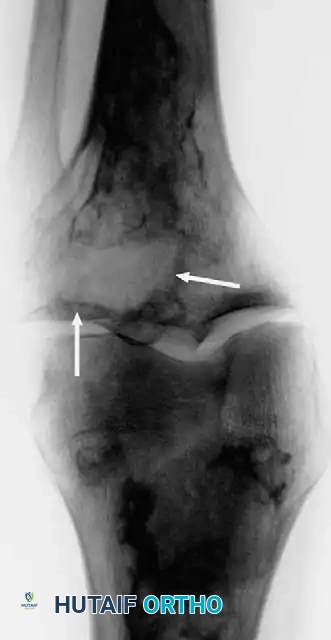

Anteroposterior and lateral radiographs of the knee of a 58-year-old man with malignant fibrous histiocytoma showing an aggressive area of bone destruction adjacent to multiple bone infarcts. Despite this appearance, the patient was treated for 6 months for degenerative joint disease before referral.

Radiographically, these tumors exhibit a highly aggressive appearance. They are typically purely lytic with indistinct, permeative borders (a wide zone of transition). They may appear as an area of aggressive bone destruction adjacent to an otherwise typical area of Paget disease or a calcified bone infarct. Periosteal reaction (such as Codman's triangle or a "sunburst" pattern) is notably absent unless a pathological fracture has already occurred.